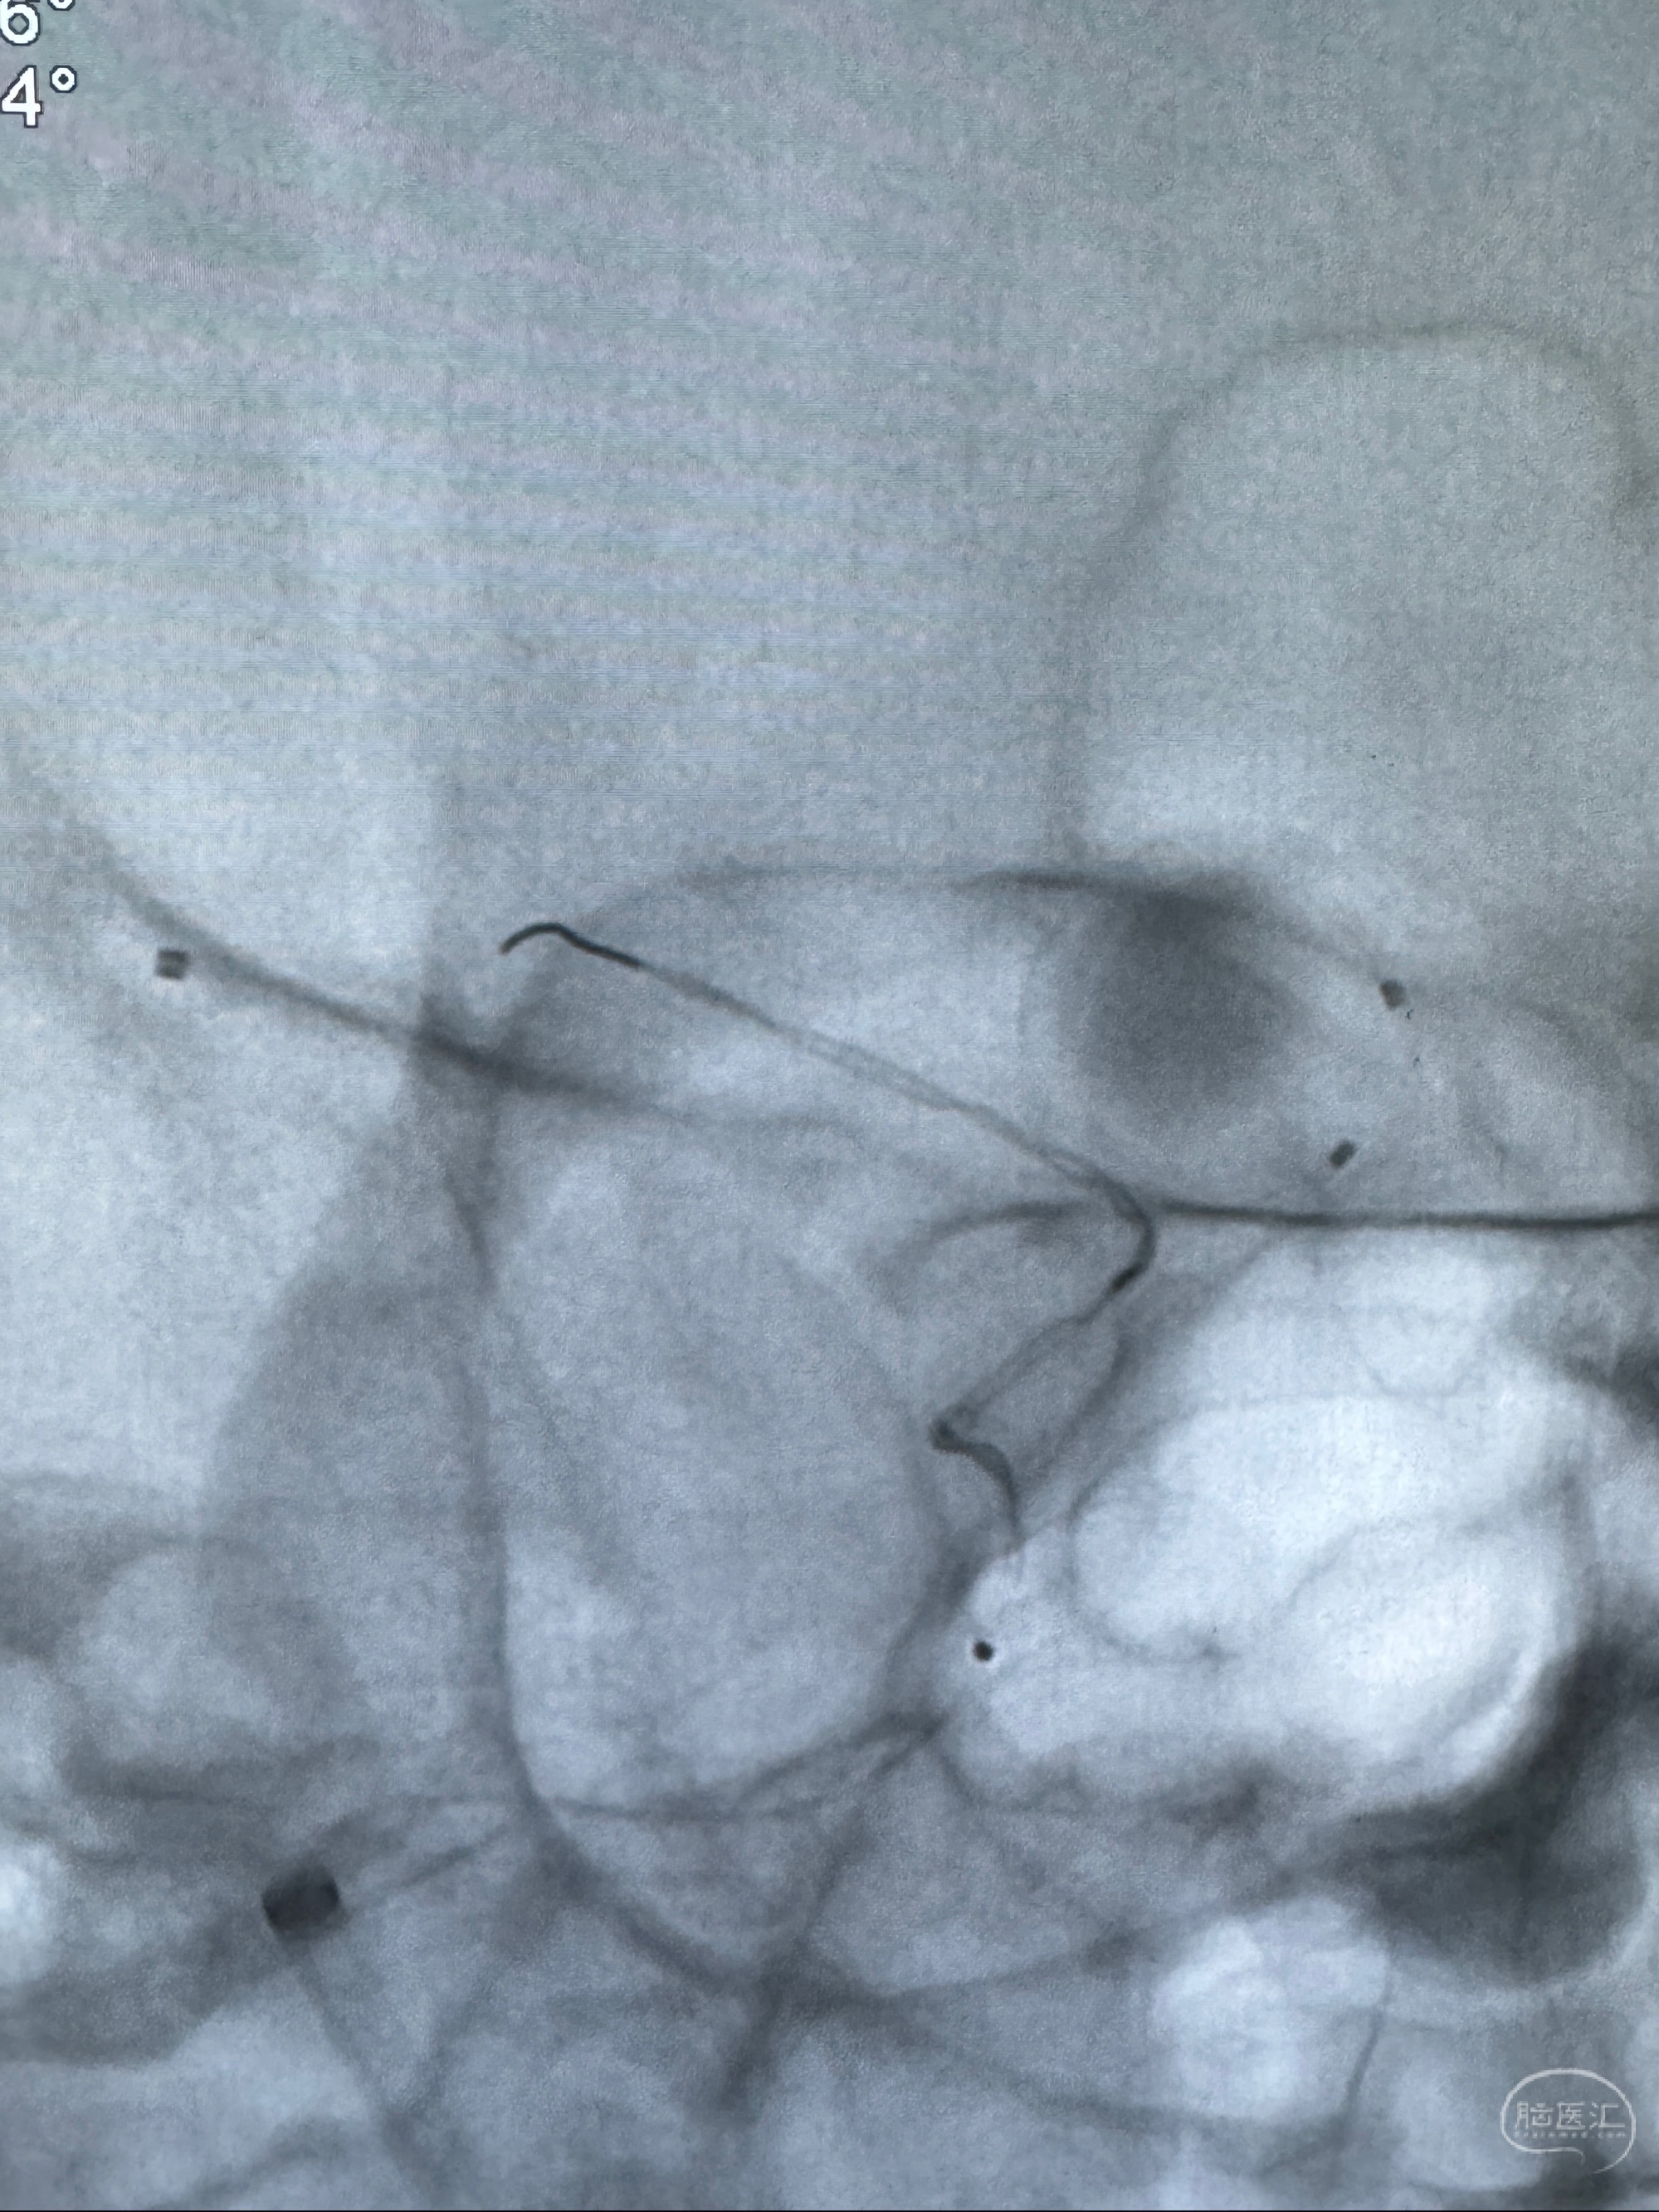

透视可见红圈部分为支架导管的头端

手推冒烟显示支架位置及展开情况,箭头为支架导管的位置

尝试回收支架失败,只能考虑释放支架了

逐帧图像展示歪着脖子释放支架,旁边吩咐助手手机摄影、拍照留像(透视机不能留影像)

接下的视频为释放支架的过程及试图确认支架与血管的关系